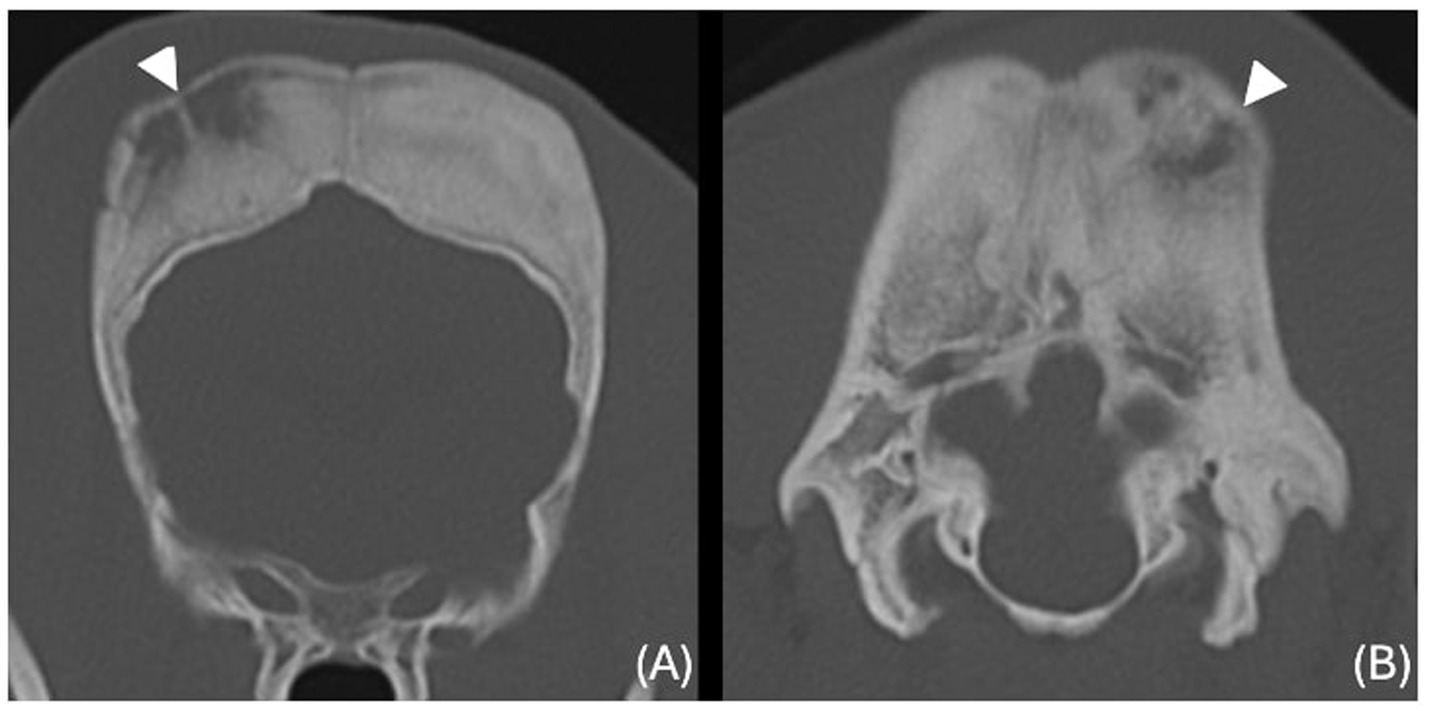

The images revealed severe, bilateral and symmetrical thickening of the parietal, occipital and frontal bones, as well as the squamous part of the left temporal bone (Figure 1, white arrows). The lesions were characterised by prominent bone sclerosis, which appeared lamellated in some areas, as well as more focal irregular areas of hypoattenuation with punctate lysis of the cortex (at the right frontal, left parietal, and left occipital bones) (Figure 2, white arrowheads). The osteopenic areas were occupied by mixed soft tissue and fluid attenuation with patchy contrast enhancement (Figure 3, black arrows). Irregular margination with smooth periosteal reaction of the intracranial side of the occipital and parietal bones was also noted. The os tentorium was thickened and sclerotic, especially on the left side.

Figure 2. Transverse CT images of the frontal (A) and occipital (B) bones (window level 300HU, widow width 1500HU) unenhanced, showing ill-defined hypoattenuating regions with punctate cortical lysis (white arrowheads).